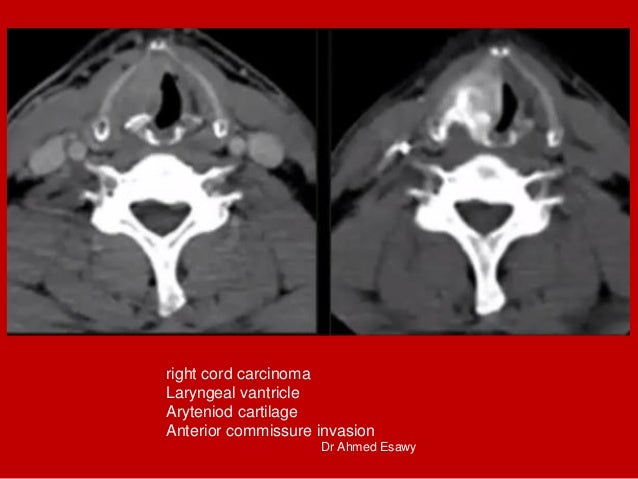

33. 33. right cord carcinoma Laryngeal vantricle Aryteniod cartilage Anterior commissure invasion Dr Ahmed Esawy